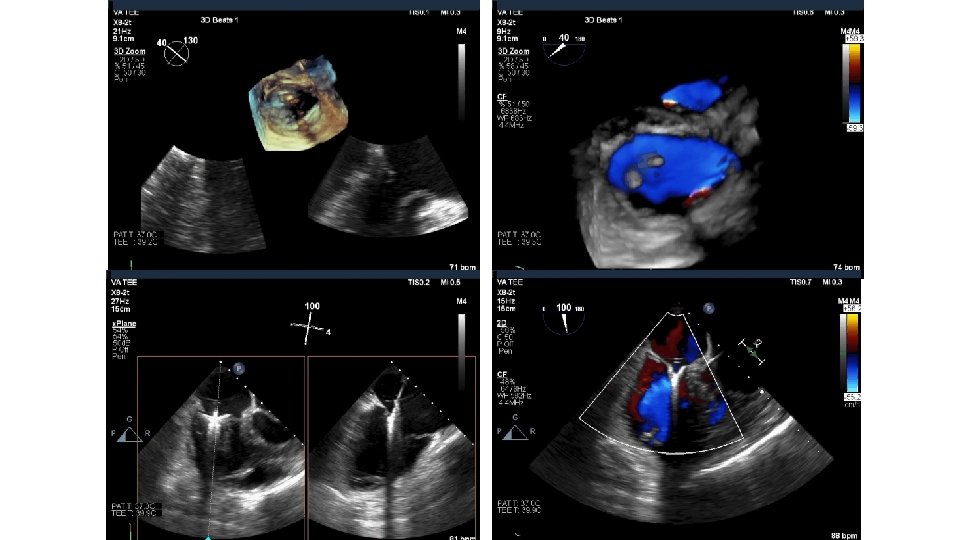

Tricuspid Valve (TV) Imaging • TV imaging is challenging • Three TV leaflets (anterior, septal and posterior) are thin and membranous Huitin et al. Archives of Cardiovascular Diseases Volume 109, Issue 1, January 2016, Pages 67 -80

• TV assessment • severity of TR • Mechanism of • mode of leaflet coaptation, • degree of tricuspid annulus enlargement and tenting • TAPSE • 3 D-TEE • Cardiac CT • cardiac MRI

80 yo male with mild dementia referred for evaluation of Progressive dyspnea >1 year Exam: venous distention, TR murmur, no RV lift Creat 2. 2 Transthoracic Echo: Isolated severe TR. IVC 3. 3 cm. RA is dilated RV normal function. Dilated annulus (4. 2 cm)-presumed mechanism of TR. TEE, right heart catheterization RAP 16, and coronary angiography: non obstr CAD What do you do next? Medical management, Refer to CV surgery , other options